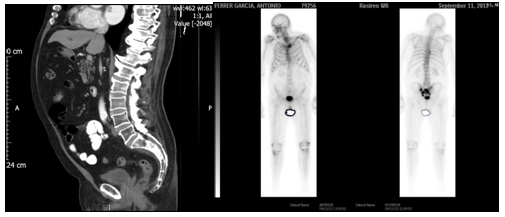

Clinical story: In 2009, was diagnosed of prostate cancer with PSA 6.82 ng/mL, Gleason 6, and clinical CT staging T3bN1M0 by evolvement of seminal vesicle and an iliac node. Treated with External Beam 3D-Conformed Irradiation over pelvis, seminal vesicles and prostate plus androgenic deprivation for 24 months. After 30 months of follow-up, PSA is elevated (10 ng/mL) with asymptomatic patient. A new thoracic-abdominal-pelvic CT study is performed, as bone-scan, which shows osteoblastic metastatic bone disease in sacral location and left sacral-iliac joint (Figure 1). Hormone treatment is reintroduced with complete androgenic deprivation, achieving an auspicious biological response with the descent of PSA quantification (3.83 ng/mL).

Figure 1 CT scan shows Osteoblastic metastatic bone disease in sacral location and left sacral-iliac joint.